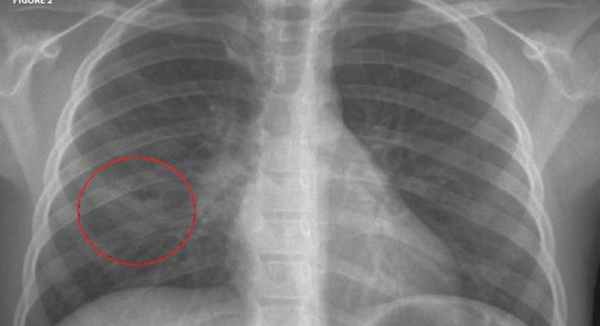

- Рентген грудной клетки. Обычно поставить верный диагноз помогает обзорная рентгенограмма в переднезадней проекции. На снимке хорошо видна локализация переломов и их количество.

- обзорная рентгенография грудной клетки, которая позволяет уточнить локализацию, характер и степень травмы, выявить наличия воздуха или крови в плевре;

Пальпация грудной стенки может выявить наличие нескольких переломов ребер. Некоторые врачи считают, что у здоровых пациентов с незначительной травмой адекватной является клиническая оценка. Тем не менее, для пациентов с клинически значимой тупой травмой обычно проводят рентгенографическое исследование грудной клетки, с целью выявления сопутствующих травм (например, пневмоторакса, ушиба легких Ушиб легкого Ушибом легкого называют посттравматическое кровоизлияние и отек легких без разрыва. (См. также Обзор торакальной травмы (Overview of Thoracic Trauma)). Ушиб легкого является частой и потенциально. Прочитайте дополнительные сведения ). Многие переломы ребер не заметны на рентгенограммах грудной клетки; в этих случаях могут быть проведены специфические исследования визуализации ребер, но идентификация всех случаев переломов ребер с использованием рентгенографии не является необходимой. Выполняют другие тесты, направленные на выявление сочетанных повреждений, заподозренных клинически.